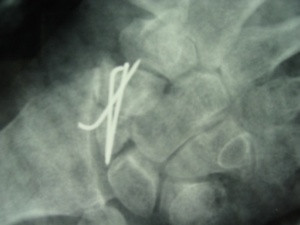

ASSOLUTAMENTE CHIRURGICO. Toelette delle superfici di frattura, seguita da innesto osseo, cortico-spongioso, di solito prelevato dalla cresta iliaca, sintesi con vite o Kirschner o cambre, immobilizzazione in apparecchio gessato o tutore, ciclo riabilitativo. I risultati sono buoni.

Pseudoartrosi

Casi trattati con innesto osseo,osteosintesi e immobilizzazione